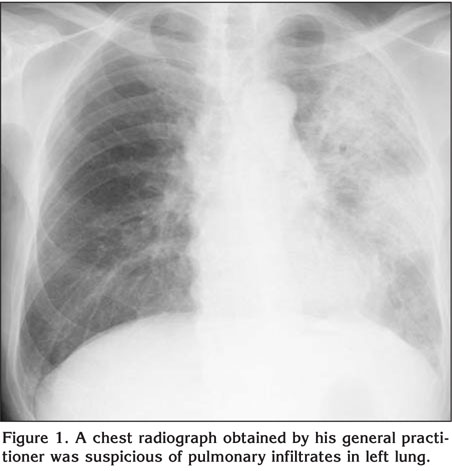

An 83-year-old man presented with a 10-day history of non-productive cough, fever, and general fatigue. The patient smoked for 67 year one pack a day but he was not exposed to toxins, tropical diseases and legal or illegal drugs. A chest radiograph obtained by his general practitioner was suspicious of pulmonary infiltrates in left lung (Figure 1). The physical examination was unremarkable. No lymphadenopathy was present. Laboratory data were remarkable for white cell count of 16.4 x 109/L with 18% eosinophils. No biliary parasite was identified by sonography. Egg of parasite was not found in the stools and serological tests were negative for parasites. The chest computerized tomography scan on showed a consolidation in upper and lower lobes of the left lung. The distribution of the infiltrates was nonsegmental. All tests for acid-fast bacilli including culture were negative. Serologic and microscopic testing for fungi was negative. Cytoplasmic and perinuclear antineutrophil antibodies were unremarkable. A bronchoalveolar lavage obtained from the left upper lobe showed total cell count 2.9 x 105/mL with 43% eosinophils; no pathogenic organism was found. Taken these results together, the diagnosis of EP was confirmed. The patient was started on 40 mg prednisolone per day. During the next 24 h he improved dramatically. After two weeks of treatment all laboratory tests and pulmonary infiltrates had normalized. He was successfully weaned off the prednisolone over a period of five months.

Figure 1